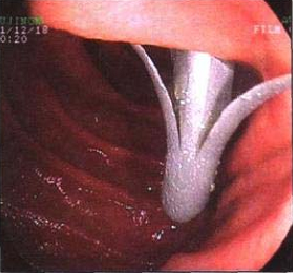

Ⅲ、POEM治疗贲门失弛缓症

⑤ESD

随着内镜微创技术的发展,越来越多的早期消化道癌、癌前病变及胃肠黏膜下疾病可完全在内镜下予以切除,免除了更大的手术创伤,这就是内镜黏膜下剥离术ESD(endoscopic submucosal dissecfion)

该治疗具有不改变消化道解剖结构、不开刀、体表无创口、创伤、出血少、恢复快等优势,是近年来国际、国内最新兴起的内窥镜下微创治疗手段之一,适用于食管、胃、十二指肠等上消化道及结、直肠的黏膜下良性肿瘤、黏膜的早期癌变以及具有癌变倾向病变的切除治疗。因其特殊的微创优势,得到广大医生及患者的推崇,是消化道黏膜及黏膜下病变治疗的新兴发展趋势。我中心已经开展该项技术,技术成熟,并还开展了经口内镜下肌切开术POEM、内镜经粘膜下隧道肿瘤切除术STER、粘膜下隧道内镜剥离术ESTD,术后病人随访,恢复良好。